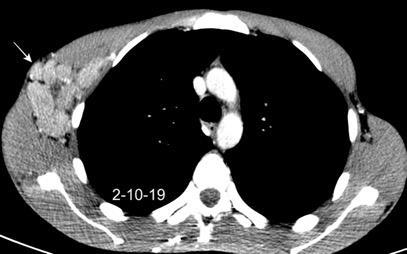

Masa axilar izquierda y derrame pleural derecho. Implantes pleurales, paraespinales . Ganglios en mamaria interna. Linfoma B difuso

Linfoma NH de cél. B. Invasión Transtorácica.

Afectación axilar

Conglomerado adenopático axila derecha. Linfoma de Hodgkin.